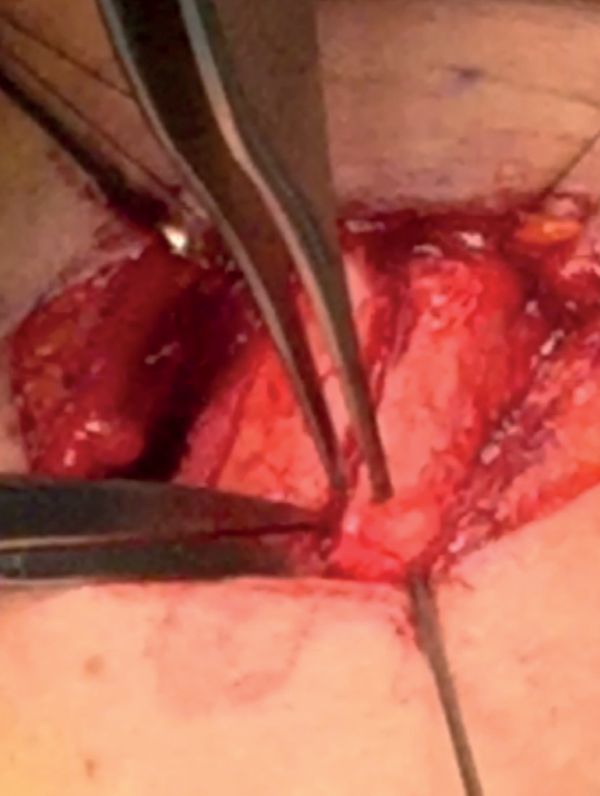

Inserting the titanium bridge

The superior and inferior bridges are inserted in no particular order. The bridge is grasped with a small non-tooth forcep from its holes and gently slides in (Figure 16). The edge of the bridge should lie flush with the edge of the thyroid laminae. There may be some resistance from the perichondrium or a thick cartilage when inserting the bridge. The perichondrium can be further elevated by sharp dissection by another 1mm in the area if the resistance is felt.

Figure 16: Inserting the titanium bridge.